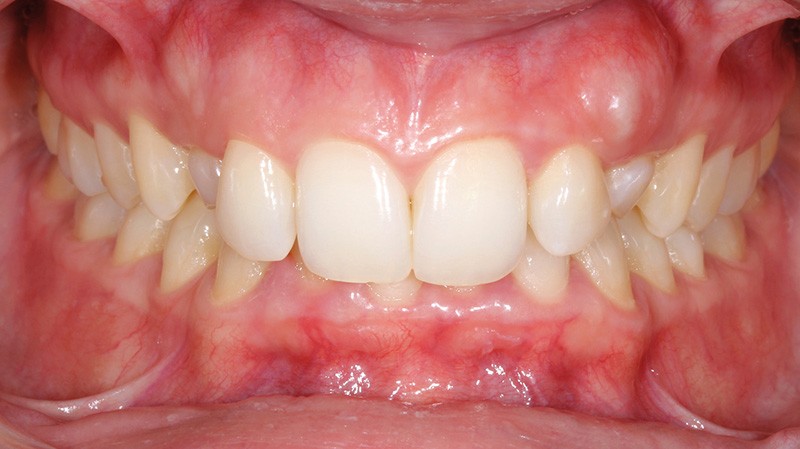

Aline se présente à la consultation pour une demande esthétique concernant ses deux canines lactéales qu’elle trouve trop petites et trop blanches (fig. 1a). Elle présente une classe II squelettique légère sur un schéma méso-divergent. D’un point de vue dentaire, une supraclusion est associée à une classe II d’Angle complète à gauche et de 4 mm à droite. Les canines maxillaires sont incluses (une vestibulaire et une palatine), avec persistance de leurs dents lactéales sur l’arcade (fig. 1b-h).

Un protocole orthodontico-chirurgical avec avancée mandibulaire est envisagé pour assurer un bon soutien labial, mais cette option est refusée par la patiente qui craint un visage trop carré. Concernant l’inclusion des canines maxillaires définitives, plusieurs thérapeutiques sont envisageables : 53, 63, 13, 23, ou 53, 63, 14, 24 peuvent être extraites, avec pour conséquence une classe II thérapeutique au niveau des molaires en fin de traitement. Cependant, la patiente souhaite mettre en place ses canines incluses pour conserver tout son capital dentaire et rétablir un idéal fonctionnel et esthétique au niveau des dents antérieures (fig. 2).